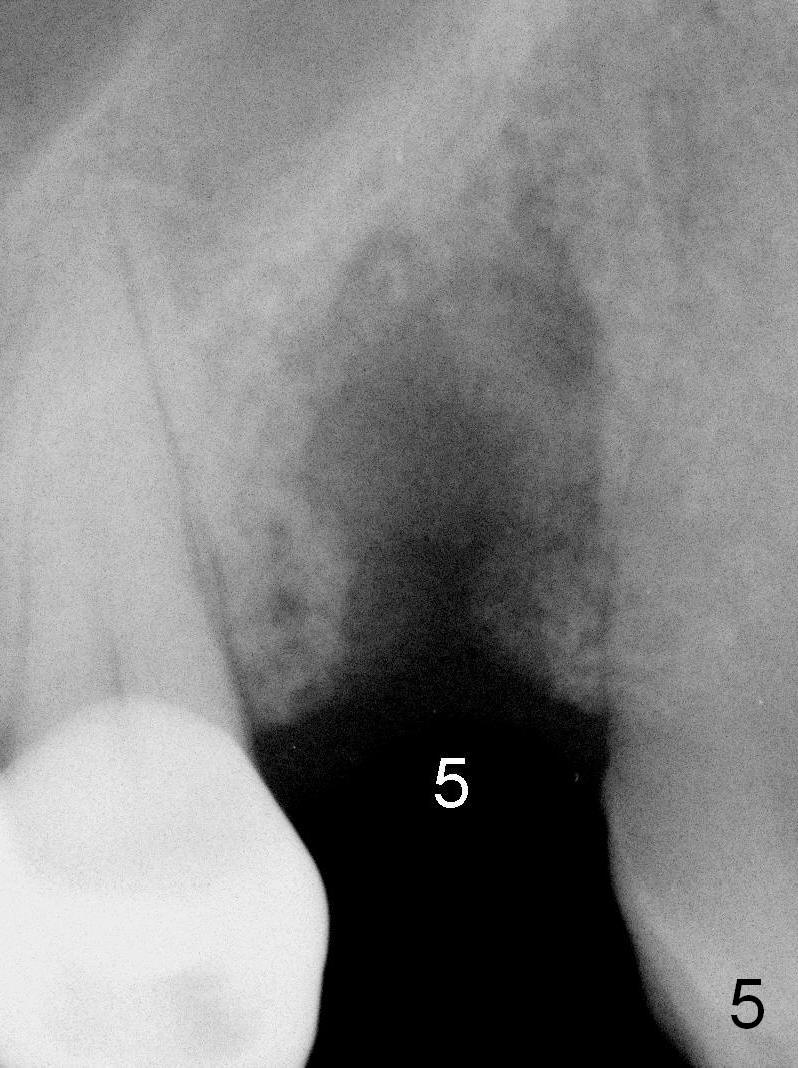

A 68-year-old man has pain and swelling associated with the tooth #5 (Fig.1). The fistula (*) is connected to the periapical radiolucency using a gutta percha (Fig.2 <). There are deep pockets distobuccal and lingual. The lingual root is found to have oblique fracture upon extraction. The distobuccal plate perforates (Fig.3). Collagen plug is placed. The buccal plate is concave (Fig.4) and socket density is low 2.5 months post extraction. Three months post extraction a 4.5x8 mm Bicon implant is placed after reamer and osteotome osteotomy (Fig.6). Bone density around the implant appears to increase 5 months post placement (Fig.7). Porcelain-fused-to-metal crown is cemented 2 weeks later. Bucco-occlusal porcelain chips 2 months post cementation. The patient decides to redo the crown. PA is taken before crown removal (Fig.8: 3 year 10 months post cementation). When a straight abutment is removed (Fig.9 A), a 15° angled abutment has to be used (Fig.10 red) for restoration.